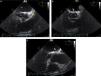

No ecocardiograma observa‐se uma imagem de massa arredondada com paredes calcificadas, assente sobre a aurícula esquerda (onde é ligeiramente compressiva) e o sulco auriculoventricular das paredes lateral e anterior, cuja fibrocalcificação parece envolver o miocárdio do segmento basal da parede lateral (mais fino, hiperecogénico e acinético) (Figura 2). A angio‐TC descreve a lesão dentro do saco pericárdico em posição alta e com amplo contacto com o pericárdio sugerindo epicentro nesta estrutura. A lesão aparenta ter uma origem extravascular podendo ser de origem sequelar a traumatismo antigo (Figura 3).